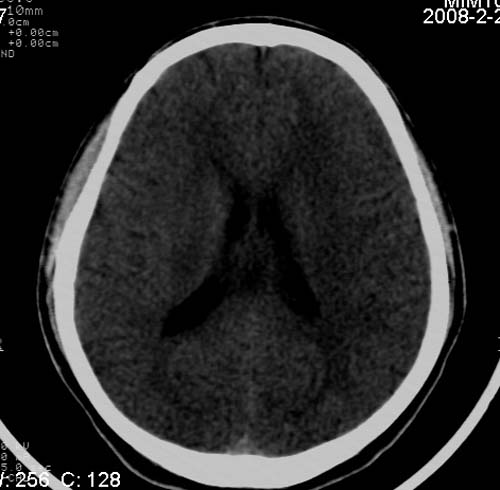

男,17岁,3天前与人斗殴,自述头痛、头晕。无恶心、呕吐,无阳性体征,一般情况良好。

病灶以钙化为主,无明显占位效应,病灶周围无水肿,这种情况应该是脑血管畸形,最多见的是动静脉畸形,其次是海绵状血管瘤.

病人较年轻,有头疼、头晕症状,动静脉畸形可能性大。